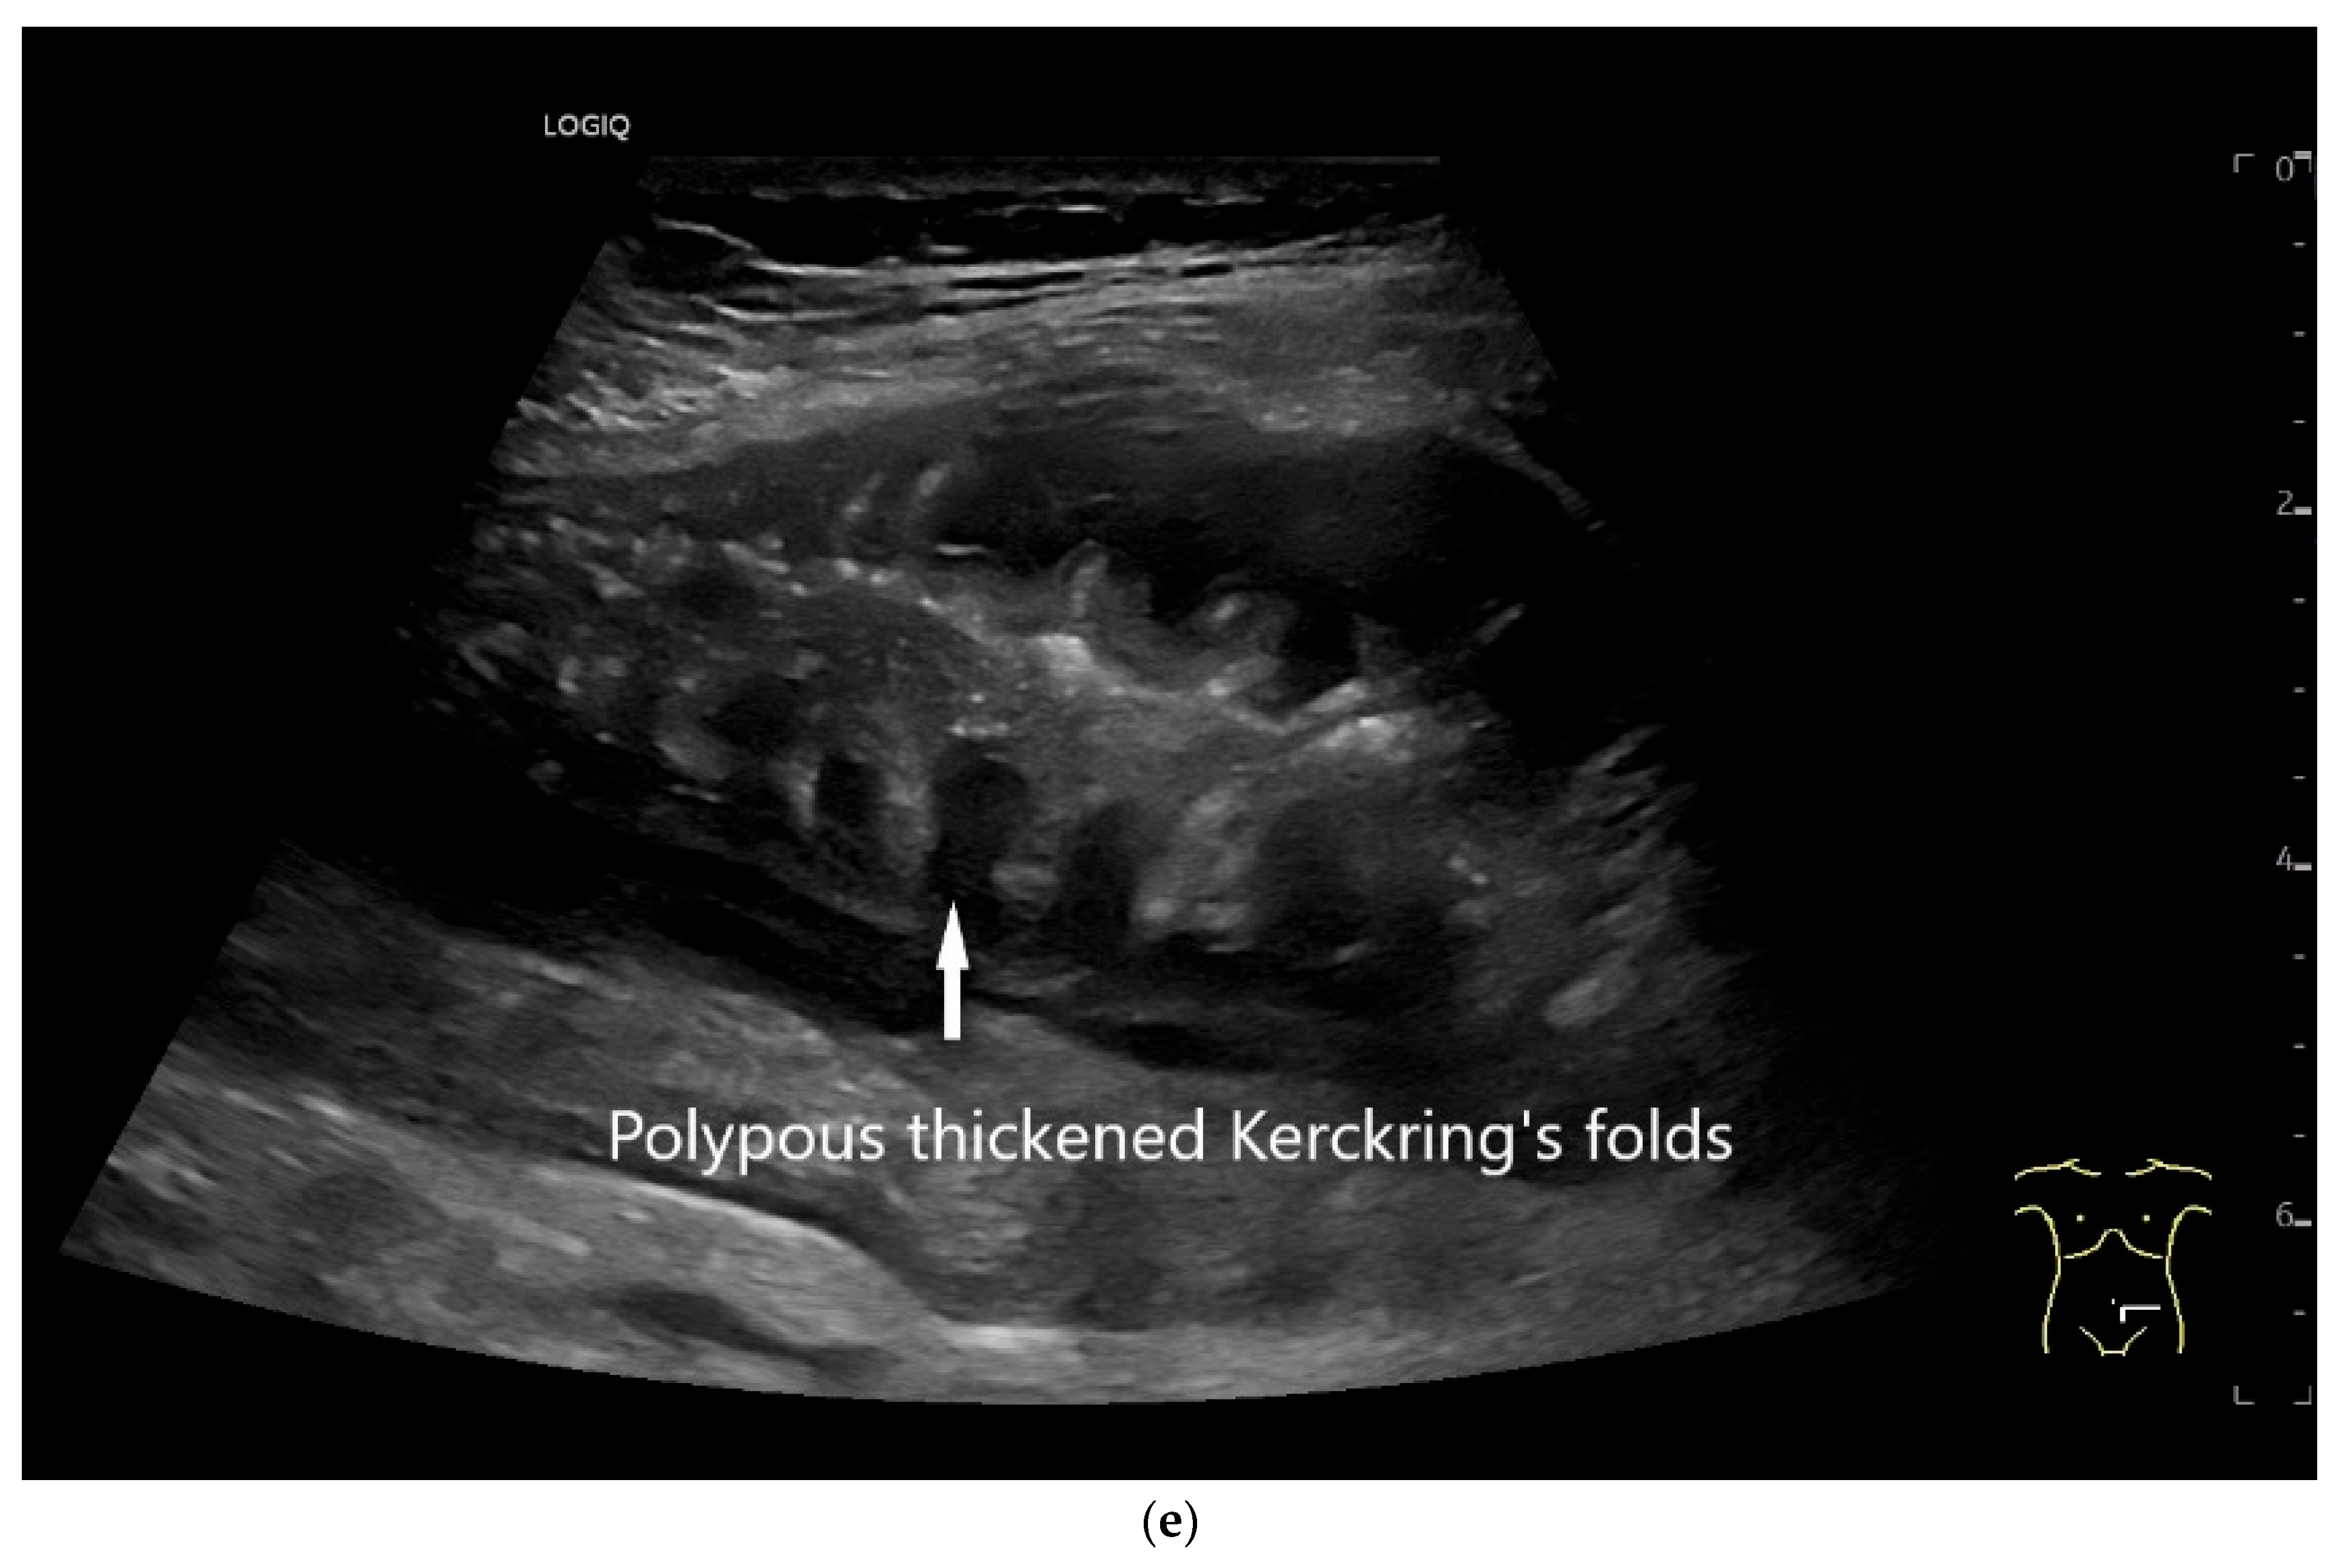

Figure 9.

Burkitt-Lymphoma. In a patient with weight loss, increased abdominal circumference, anemia, and physical weakness, the initial sonographic examination reveals an extensive tumor with intense hypoechogenicity and a connection to the jejunum in the left mid-abdomen. Despite its pronounced hypoechogenicity, a feeding vessel on CDI indicates a solid character (a). The tumor significantly thickens the wall and is intensely hypoechoic. The arrows point to the multisegmental hypoechoic wall thickenings (b). Normal wall structures are still visible (W), and the tumor extends beyond the wall (arrow) (c). In addition to delicate Kerckring folds (KF), there are significantly polypoid thickened KF with pronounced hypoechogenicity (d). The thickening of KF is very extensive (e). Wall thickening was found also in the stomach and colon and allowed endoscopic biopsy to establish the diagnosis.